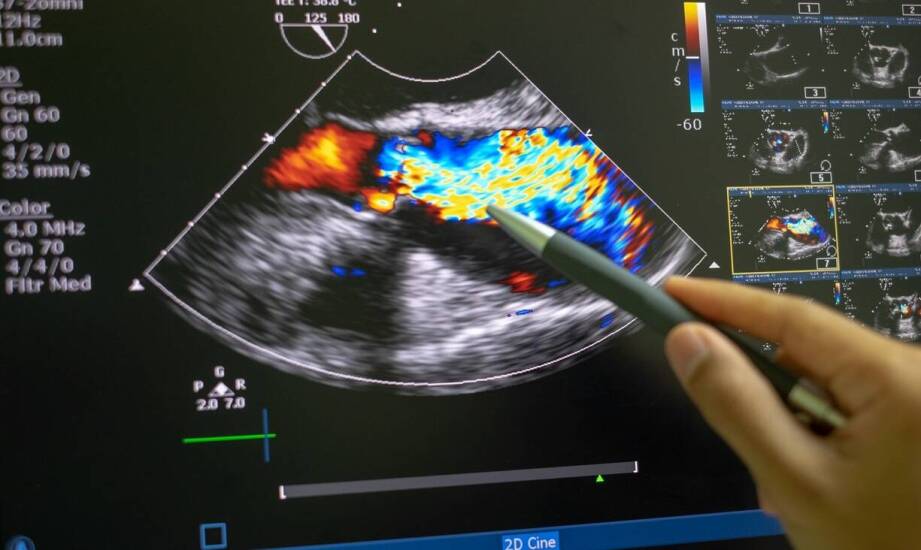

Ultrasonografia odgrywa kluczową rolę w codziennej praktyce ginekologicznej, wspierając lekarzy w różnych aspektach diagnostyki oraz monitorowania stanu pacjentek. Dzięki temu narzędziu specjaliści mogą monitorować rozwój ciąży, co jest szczególnie istotne dla zdrowia matki i dziecka. USG pozwala również na diagnozę chorób narządów płciowych, takich jak torbiele czy guzy, co umożliwia wdrożenie odpowiedniego leczenia. Ponadto, badanie to wykorzystuje się do oceny przebiegu terapii oraz prowadzenia pessaroterapii u kobiet z problemami związanymi z ciążą.

USG a leczenie chorób kobiecych odgrywa kluczową rolę w monitorowaniu oraz terapii schorzeń takich jak endometrioza czy zespół policystycznych jajników. Dzięki tym badaniom specjaliści mogą ściśle monitorować postęp choroby oraz dostosowywać leczenie do indywidualnych potrzeb pacjentek. Regularne badania ultrasonograficzne pozwalają na ocenę skuteczności stosowanych metod, co jest szczególnie istotne w przypadku terapii hormonalnej czy chirurgicznej.